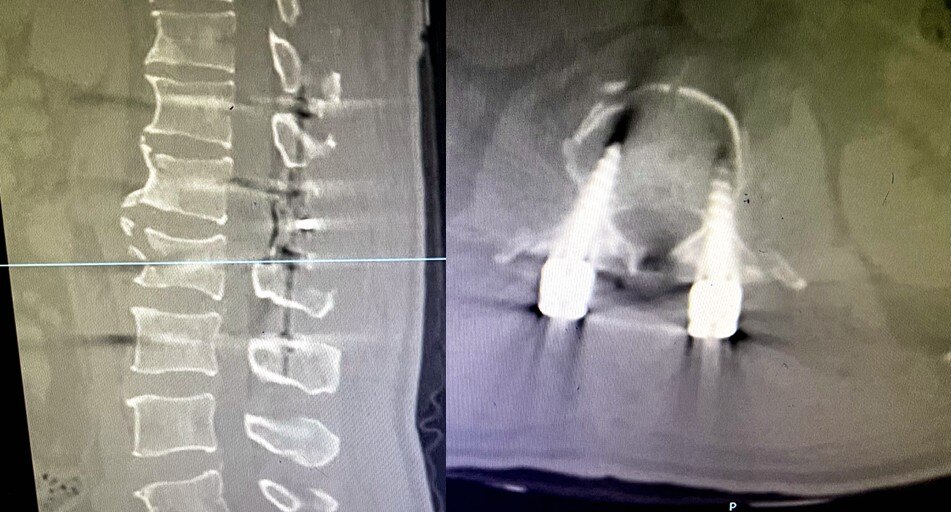

根据董先生的情况,江伟主任对他实行显微镜下减压固定融合手术,术中不仅给予脊髓精准、彻底的减压,同时注重恢复脊柱序列,确保脊髓功能正常。

术后:骨折复位固定、脊柱序列恢复、椎管减压良好